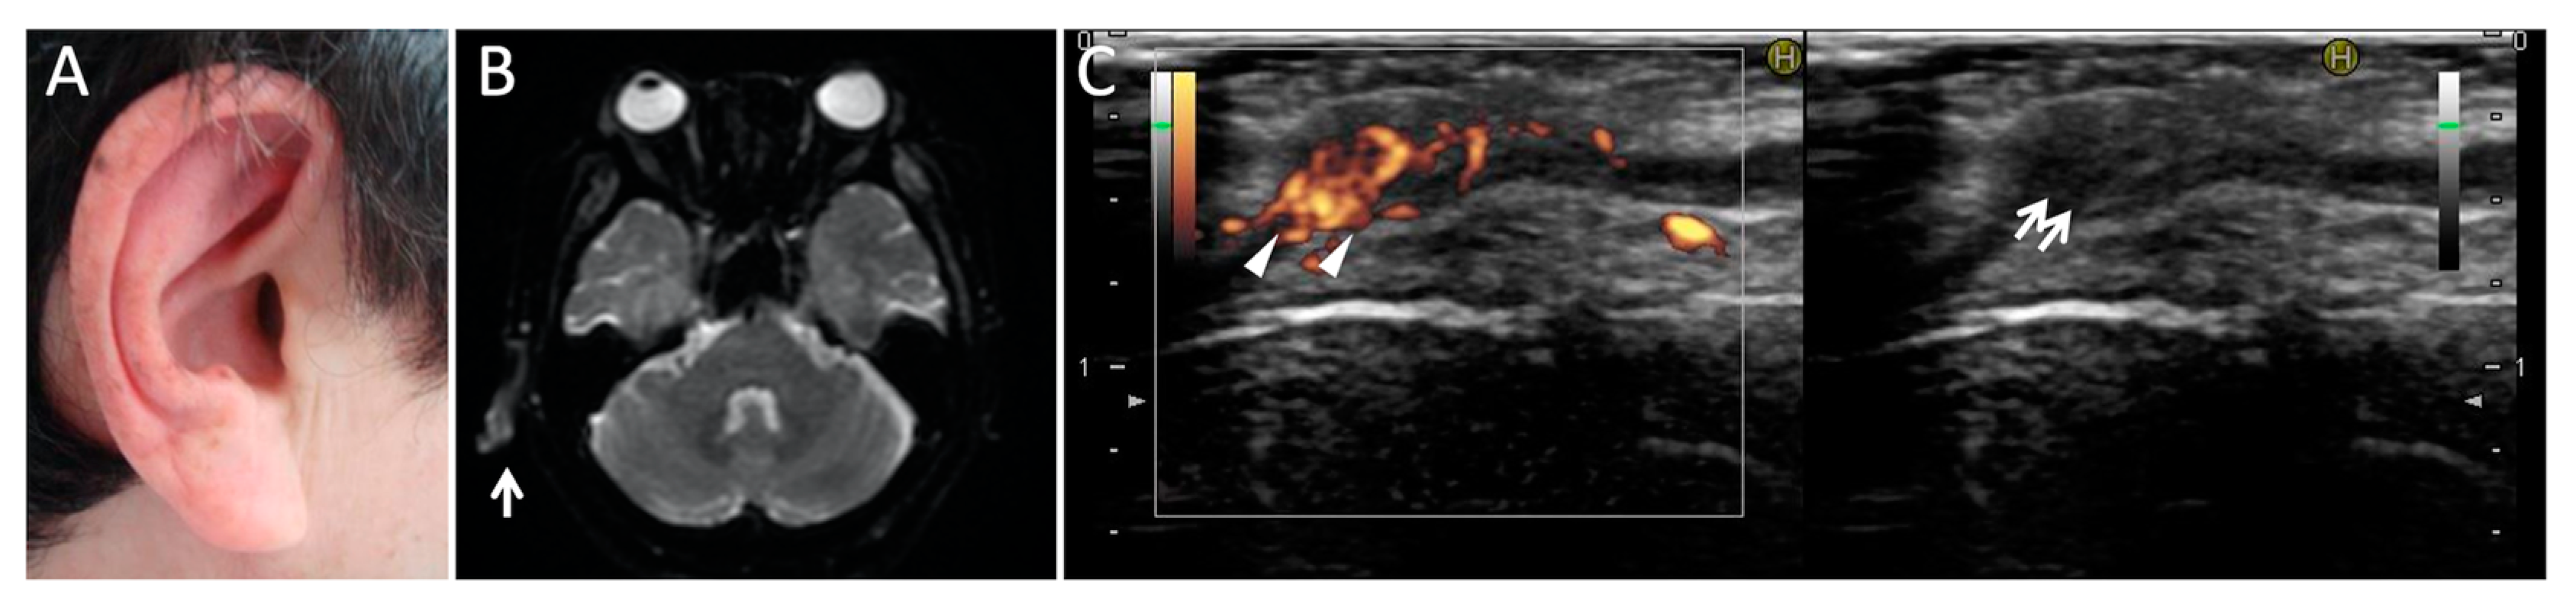

- Kuwabara, M.; Shimono, T.; Toyomasu, M.; Shioyama, M.; Mitsui, Y.; Yoshinaga, E.; Kawada, A.; Hosono, M.; Murakami, T.; Kusunoki, S. “Prominent ear sign” on diffusion-weighted magnetic resonance imaging in relapsing polychondritis. Radiat. Med. 2008, 26, 438–441. [Google Scholar] [CrossRef] [PubMed]

- Taniguchi, Y.; Nishikawa, H.; Nakayama, S.; Amano, E.; Terada, Y. Clinical implications of ultrasonography in monitoring disease activity of relapsing polychondritis. Rheumatology 2016, 55, 1250. [Google Scholar] [CrossRef][Green Version]